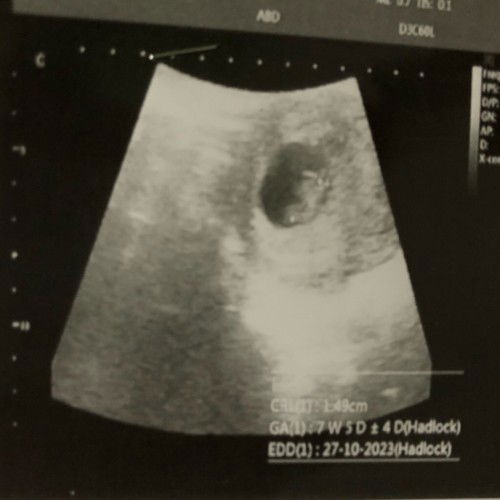

7W5D detak jantung belum terdengar

Bun kan aku baru USG, nah menurut perhitunga usia kandungan masih 7W2D tapi pas di USG 7W2D, alhamdulillah sudah keliatan janinya juga. Tapi belum kedengeran DJJ wajar gak si bund😭 mana dokternya buru-buru banget periksanya minim informasi kalau ditanya pun jawabnya kurang memuaskan😭 masih pusing, mual, dan ga doyan makan tapi payudara udah ga nyeri, takut banget janin ga berkembang😭 #worried #first_baby_